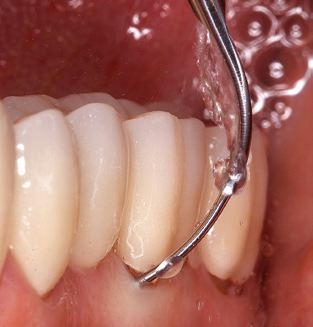

Good illumination of the working field facilitates the process considerably. The system used by the authors achieves this thanks to a 5x LED ring integrated in the handpiece. Naturally, a range of working tips for different indications is also offered. A straight, universally employable tip is the basic instrument required for machine cleaning of natural teeth (Fig. 5a and b). Curved tips, which allow access to exposed furcations, are also available for hard-to-reach areas in the posterior region (Fig. 6).

Fig. 4: Flexible probes with millimetre markings are recommended for the probing of dental implants (e.g. Colorvue Kit PCV11KIT6, Hu­Friedy). – Fig. 5a and b: A straight working tip (1P, W&H Dentalwerk Bürmoos GmbH) is a suitable instrument for use on all natural teeth. – Fig. 6: Curved working tips (3Pr/3Pl, W&H Dentalwerk Bürmoos GmbH) lend themselves to the processing of difficult-to-reach areas of the tooth and root surfaces (e.g. furcations). – Fig. 7: The tapered, hexagonal implant cleaning tip (1I, W&H Dentalwerk Bürmoos GmbH) permits atraumatic and efficient cleaning of the crown and abutment surfaces. – Fig. 8: Titanium and carbon curettes are suitable instruments for the manual cleaning of the implant surfaces.